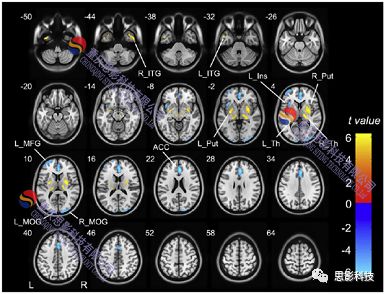

具體包括:數(shù)據(jù)轉(zhuǎn)換、圖像復(fù)位、頭動(dòng)校正、配準(zhǔn)、平滑、去除顱外體素、計(jì)算CBF等。

2.CBF統(tǒng)計(jì)計(jì)算:

1)構(gòu)建單被試廣義線性模型

2)組水平分析

統(tǒng)計(jì)比較(t檢驗(yàn)、方差分析、回歸分析等)

提取特定腦區(qū)信號(hào)與行為(臨床)數(shù)據(jù)進(jìn)行進(jìn)一步統(tǒng)計(jì)分析(如相關(guān))。

1) 以上統(tǒng)計(jì)結(jié)果可進(jìn)行可視化。